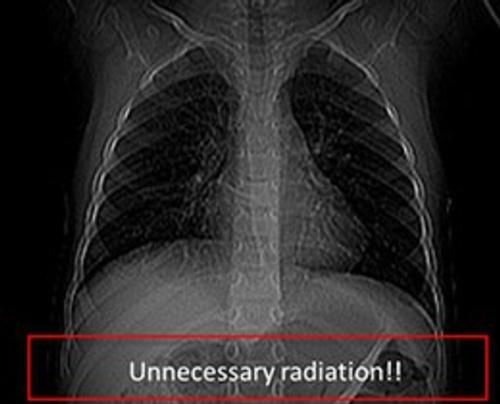

This case offers information on how to manage the radiation dose for CT examinations to provide physicians with diagnostic quality images while exposing patients to a well-controlled amount of radiation in order to obtain the images, with special emphasis on pediatric imaging. “This case is designed to provide practical explanations of some of the newer technologies and terminology associated with CT scans,” said Keith Strauss, MSc, Cincinnati Children’s Hospital Medical Center in Cincinnati, who was lead author of the case along with co-author, Marilyn Goske, MD. “It discusses radiation risk and the relationship of image quality to patient dose,” noted Strauss.

“'Child-sizing CT Dose: Optimizing Patient Care Through Quality Improvement — Pediatric and Adult Imaging’ is an excellent addition to the Image Wisely collection of educational material, and we appreciate Image Gently’s efforts to develop the case,” said Eric Gingold, PhD, director of the Image Wisely Radiation Safety Case series and member of the Image Wisely Executive Committee. “CT imaging is invaluable to medicine; however, it does expose patients to ionizing radiation. Practitioners should be cognizant of the potential risks involved and informed about the appropriate use of the technology,” he added.

Image Wisely is an initiative of the ACR, RSNA, the American Association of Physicists in Medicine and the American Society of Radiologic Technologists with the objective of lowering the amount of radiation used in medically necessary imaging studies and eliminating unnecessary procedures. Image Wisely offers resources and information to radiologists, medical physicists, other imaging practitioners and patients.